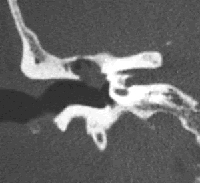

El colesteatoma es un tumor benigno del oído formado por un cúmulo de piel que crece de forma desordenada y progresiva, y que afecta inicialmente al tímpano y a los huesecillos (martillo, yunque y estribo).

Algunos de los síntomas que produce son vértigo y pérdida completa e irrecuperable de la audición, parálisis facial (si comprime el nervio que mueve la cara), meningitis y absceso cerebral, cuando invade estructuras cerebrales, o, si ha evolucionado libremente y sin tratamiento, hipocausia y supuración.

Por lo general su evolución es lenta e indolora, por eso algunos pacientes no acuden al otorrinolaringólogo hasta que la enfermedad ya ha empezado a complicarse. Su tratamiento es siempre quirúrgico mediante timpanoplastia. Se trata de una operación en la que, mediante microcirugía, se extirpa completamente el colesteatoma. En un 90% de los casos, los resultados son exitosos, especialmente si el tumor se encuentra en un estadio inicial.

Debido a la tendencia que tiene a reproducirse, el paciente debe ser controlado durante muchos años, en la mayoría de los casos, mediante una visita anual y más raramente, cada seis meses. Por otra parte, además de la extirpación completa del colesteatoma, esta operación busca conservar al máximo la audición existente y, en la medida de los posible, también la recuperación de la pérdida mediante la reconstrucción de los huesecillos del oído medio u osiculoplastia, a pesar de que a veces no sea posible